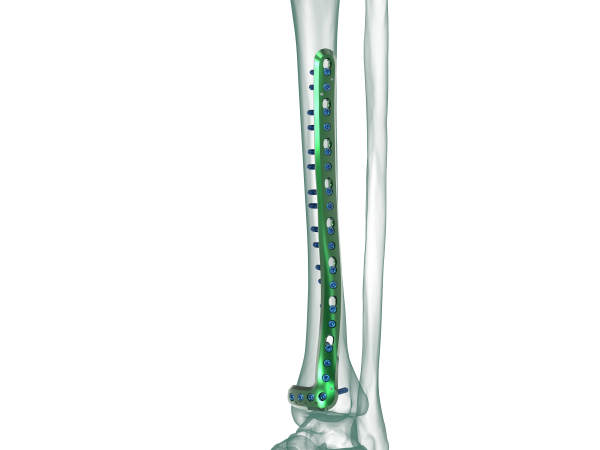

TRUE LOCK Distal Tibia Anterolateral Anatomic Plate

Anatomical plate; right & left

7 different hole option between 5-17

Combi-holes provide the flexibility of axial com- pression and locking capability throughout the length of the plate shaft.

The head of the plate features four locking holes that accept locking screws Ø 3.5 mm, cortex screws Ø 2.7 mm and Ø 3.5 mm or cancellous bone screws Ø 4.0 mm.

Anatomically shaped

Four distal head holes angle 7 degree inferiorly to capture the posterior malleolus.

Kirschner wire holes in the head, parallel to the joint, accept Kirschner wires to temporarily fix fragments and show proximity to the joint .

At the cancellous part of the bone near the joint, 4,0 mm cancellous locking screw option supports plate and screw fit well; prevents it from pull out.